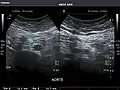

Aorta: Visualized portions normal in caliber, 16 x 15 mm.

Aorta